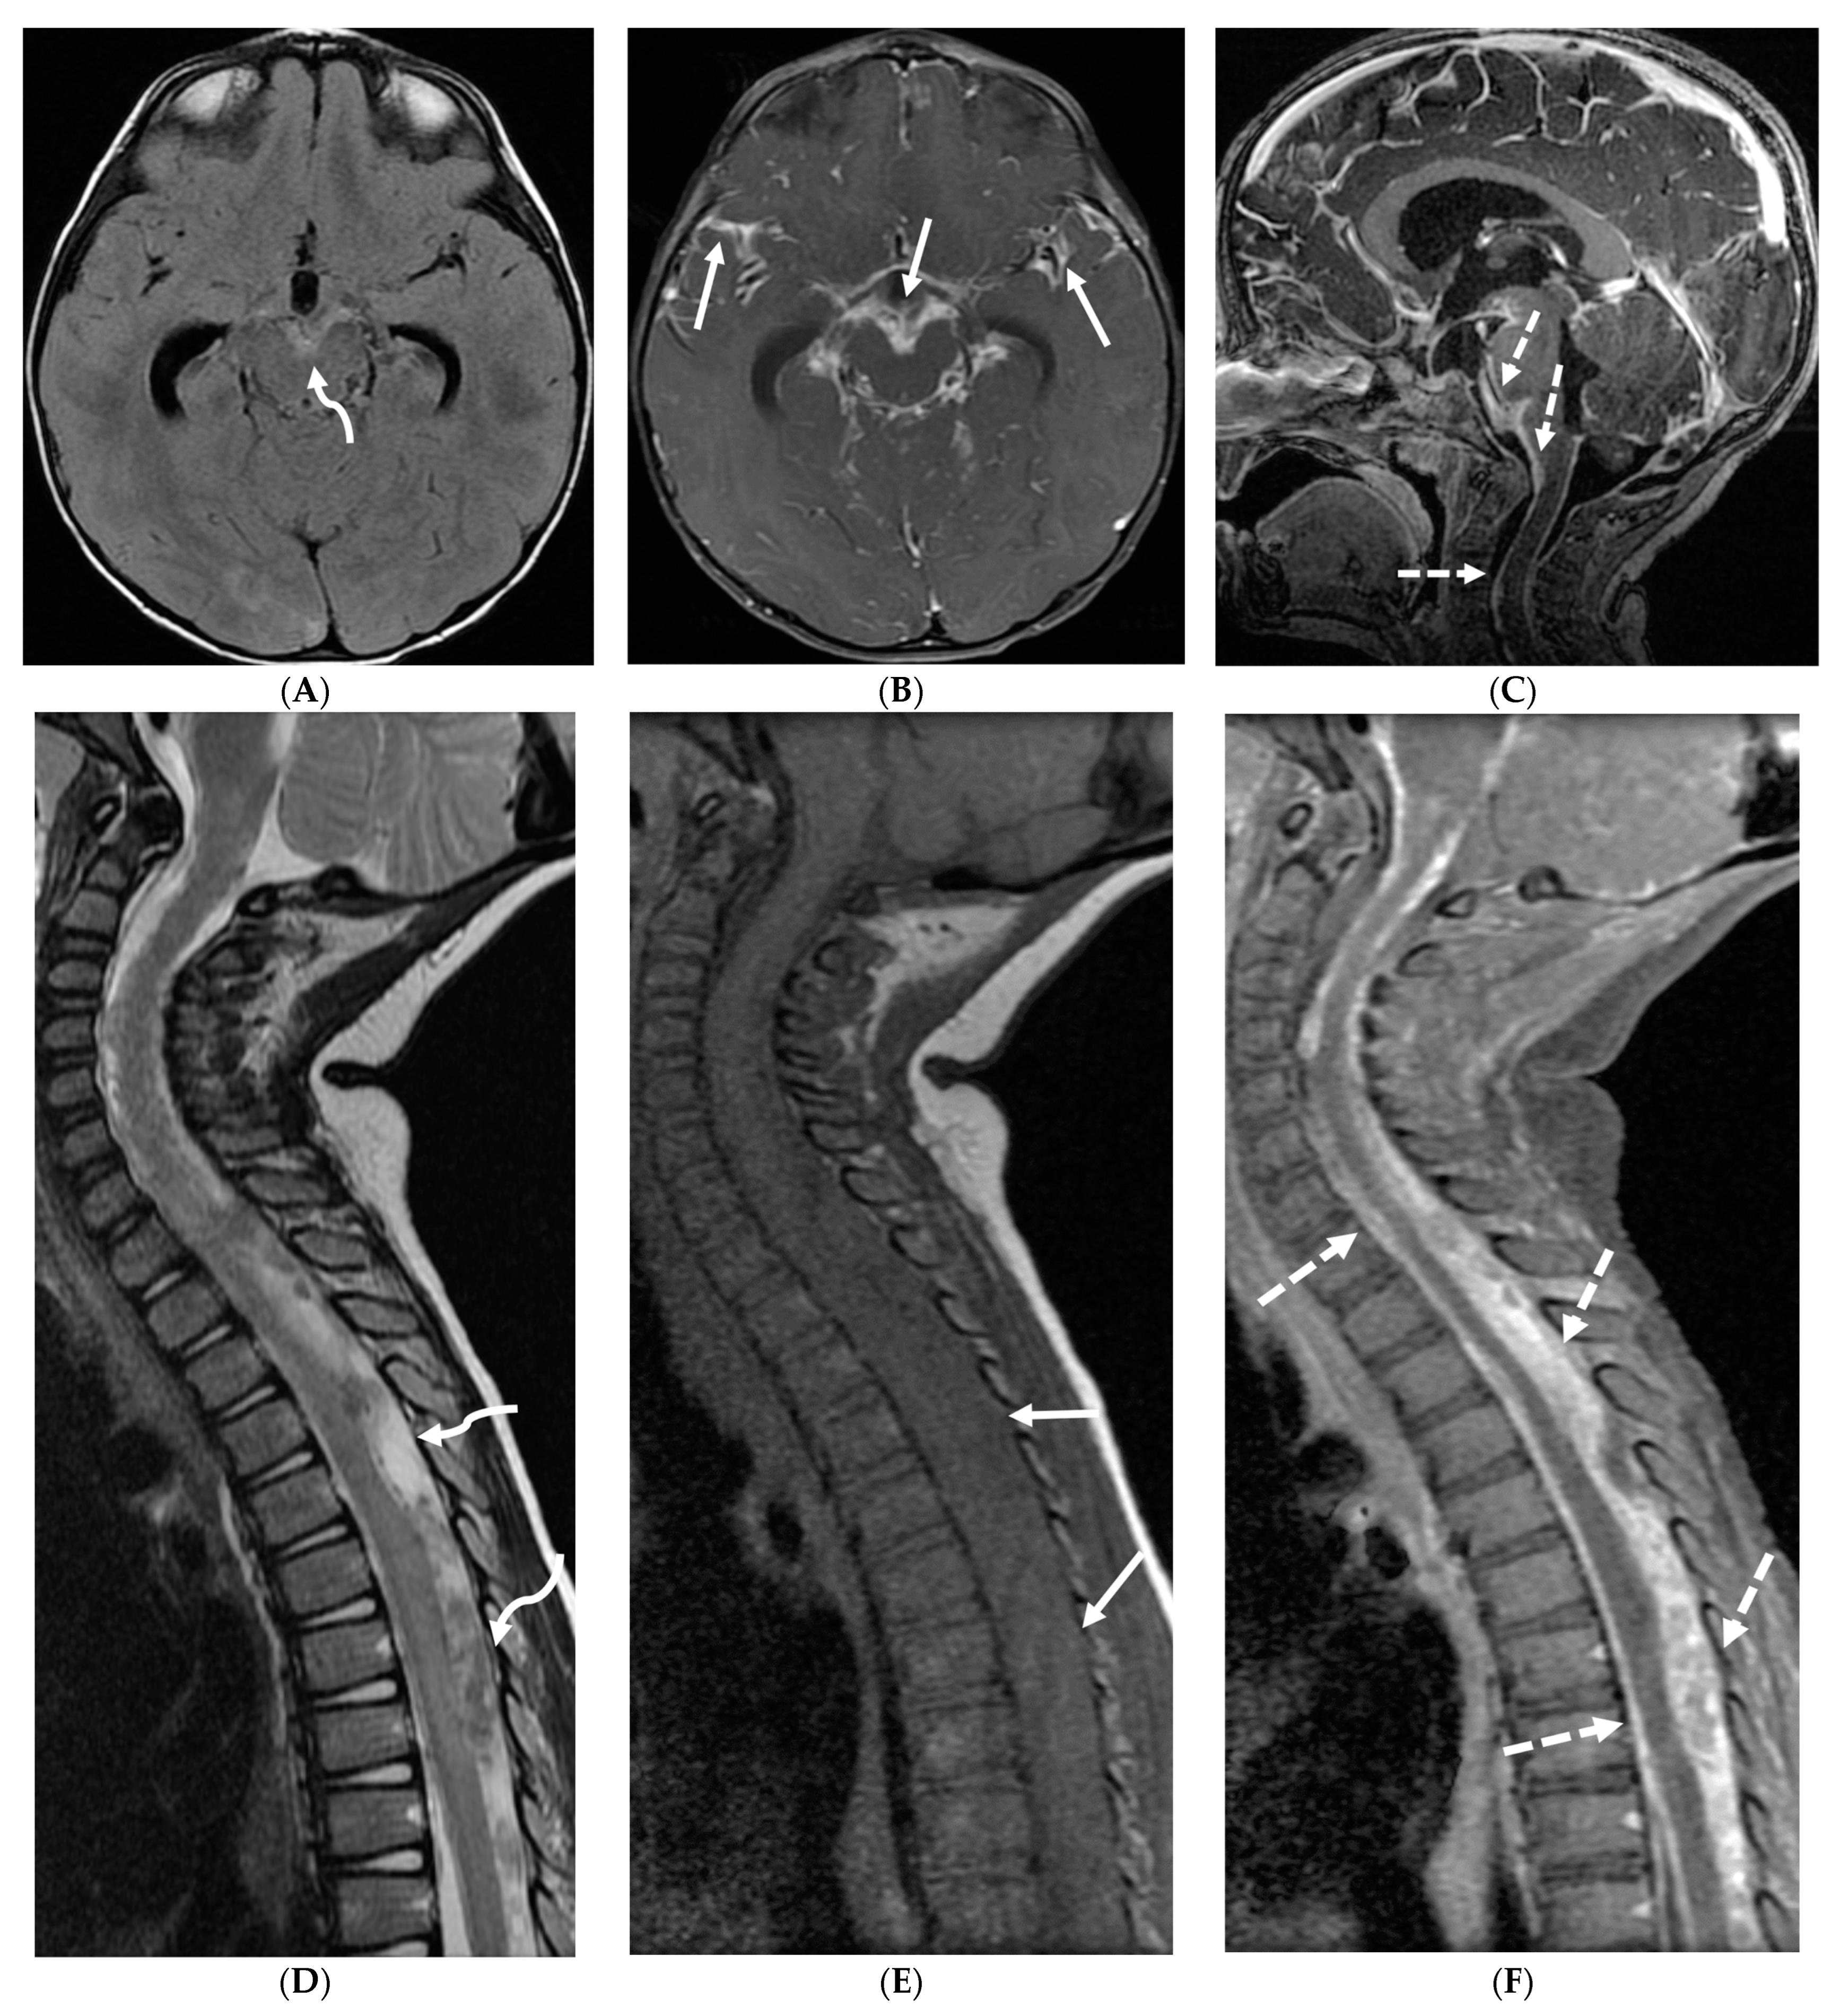

Prototheca species are unicellular algae that are typically known to involve the cutaneous and subcutaneous tissues in humans [6]. Systemic involvement, although rare, can cause meningitis, peritonitis, endocarditis, etc. and is commonly seen in immunodeficient individuals [7]. Prototheca spp. infections are usually exogenous and associated with traumatic inoculation from contaminated soil or water. They can also occur from surgery or catheterization, and even insect bites [8]. Exposure leads to chronic granulomatous inflammation with necrosis [6]. Notably, diagnosis of protothecosis may be challenging as it is not easily identified on Hematoxylin and eosin (H&E) or routine fungal stains, and mimics many fungal infections such as Coccidiodes, Blastomyces. Imaging findings include diffuse LME along the cortical sulci and spinal cord, with multiple loculations given the chronic inflammatory response. These loculations characteristically cause mass effect leading to a flattened and deformed spinal cord (Figure 2) [9].

Figure 2.

Post contrast sagittal T1 brain (A), T1 spine (B), axial T1 brain (C) and spine (D): 17-year-old girl with couple of years of fatigue, shuffling gait, back/lower extremity pain. There is moderate ventriculomegaly (white star). Meningeal enhancement is present around the cervical cord (white arrow). Flattened and deformed brainstem & spinal cord diffusely (curved arrows) and enhancing septae (dashed arrows) within the thecal sac are noted likely from chronic meningitis. Basal cistern enhancement (open arrow) and septae (arrow head) in the lateral ventricles likely reflects sequela of chronic inflammation/infection. Pathology: Prototheca Zopfil.